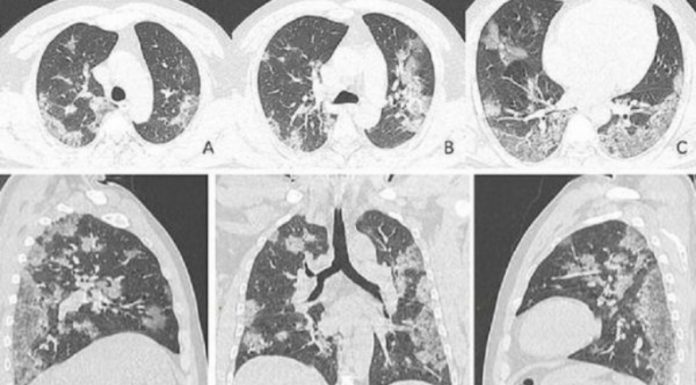

Këto imazhe me rreze X i përkasin një shtetasi kinez 44 vjeçar që vdiq nga koronavirusi. Siç mund ta shihni edhe në fotot e tmerrshme, rrezet X tregojnë shkatërrimin që sëmundja ka bërë në mushkëritë e pacientit, shkruan The Sun.

Në to shihen njolla të bardha në cepat e mushkërive, në ato që radiologët quajnë opaciteti i xhamtë, që është mbushja e xhepave të ajrit.

Këto anormalitete u identifikuan nga doktorët në skanimet e pacientëve të koronavirusit deh janë të ngjashme me ato të pacientëve që kanë vuajtur më parë gjatë epidemive të SARS e MERS. Viktima 44-vjeçare punonte në një treg prodhimesh deti në Vuhan dhe tregon qartë anormalitetin.

Skanimet tregojnë sesi lëngu në xhepat e ajrit u bë më i theksuar me kalimin e kohës siç dallohet duke krahasuar imazhet nga A deri te F.

Ky shtetas u shtrua në spital më 25 dhjetor 2019 me ethe e kollë për dy javë, e më pas u diagnostikua me pneumoni të rëndë respiratore. Megjithë trajtimet e marra ai vdiq një javë më vonë.